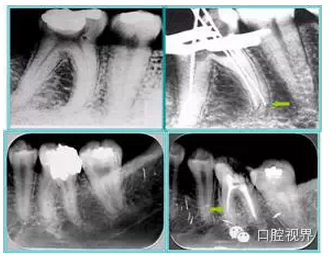

6. 術(shù)后 X 線片

術(shù)后 X 線片用來評定根管充填 長度、致密度(管壁清晰、側(cè)枝)等指標(biāo)。

左圖為根管充填術(shù)后 X 線片。圖中可見,根管充填較好。右下圖有白色小點,為側(cè)方加壓導(dǎo)致糊劑擠出所致,表明根管充填比較致密。

致密、恰到好處的充填可去除干凈根管里感染灶,機體逐漸恢復(fù)。

多根牙時候需進行偏移投照,正位投照無法說明具體哪根牙根管充填效果。